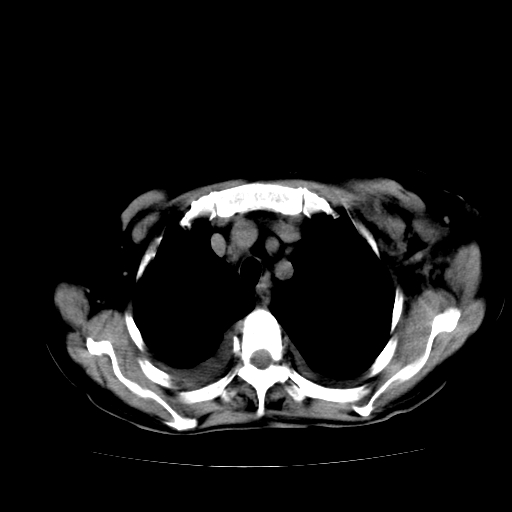

1)左侧乳腺癌并左侧腋窝及纵隔淋巴结转移,两肺淋巴道转移(癌性淋巴管炎),肝脏多发性转移。2)双侧胸腔积液。3)慢性胆囊炎。

癌性淋巴管炎,胸膜转移.肝内转移,纵隔及腋窝淋巴结转移

1、左侧乳腺癌;

2、左腋窝、纵隔淋巴结肿大(转移性);

4、双侧胸腔积液(考虑淋巴回流障碍所致);